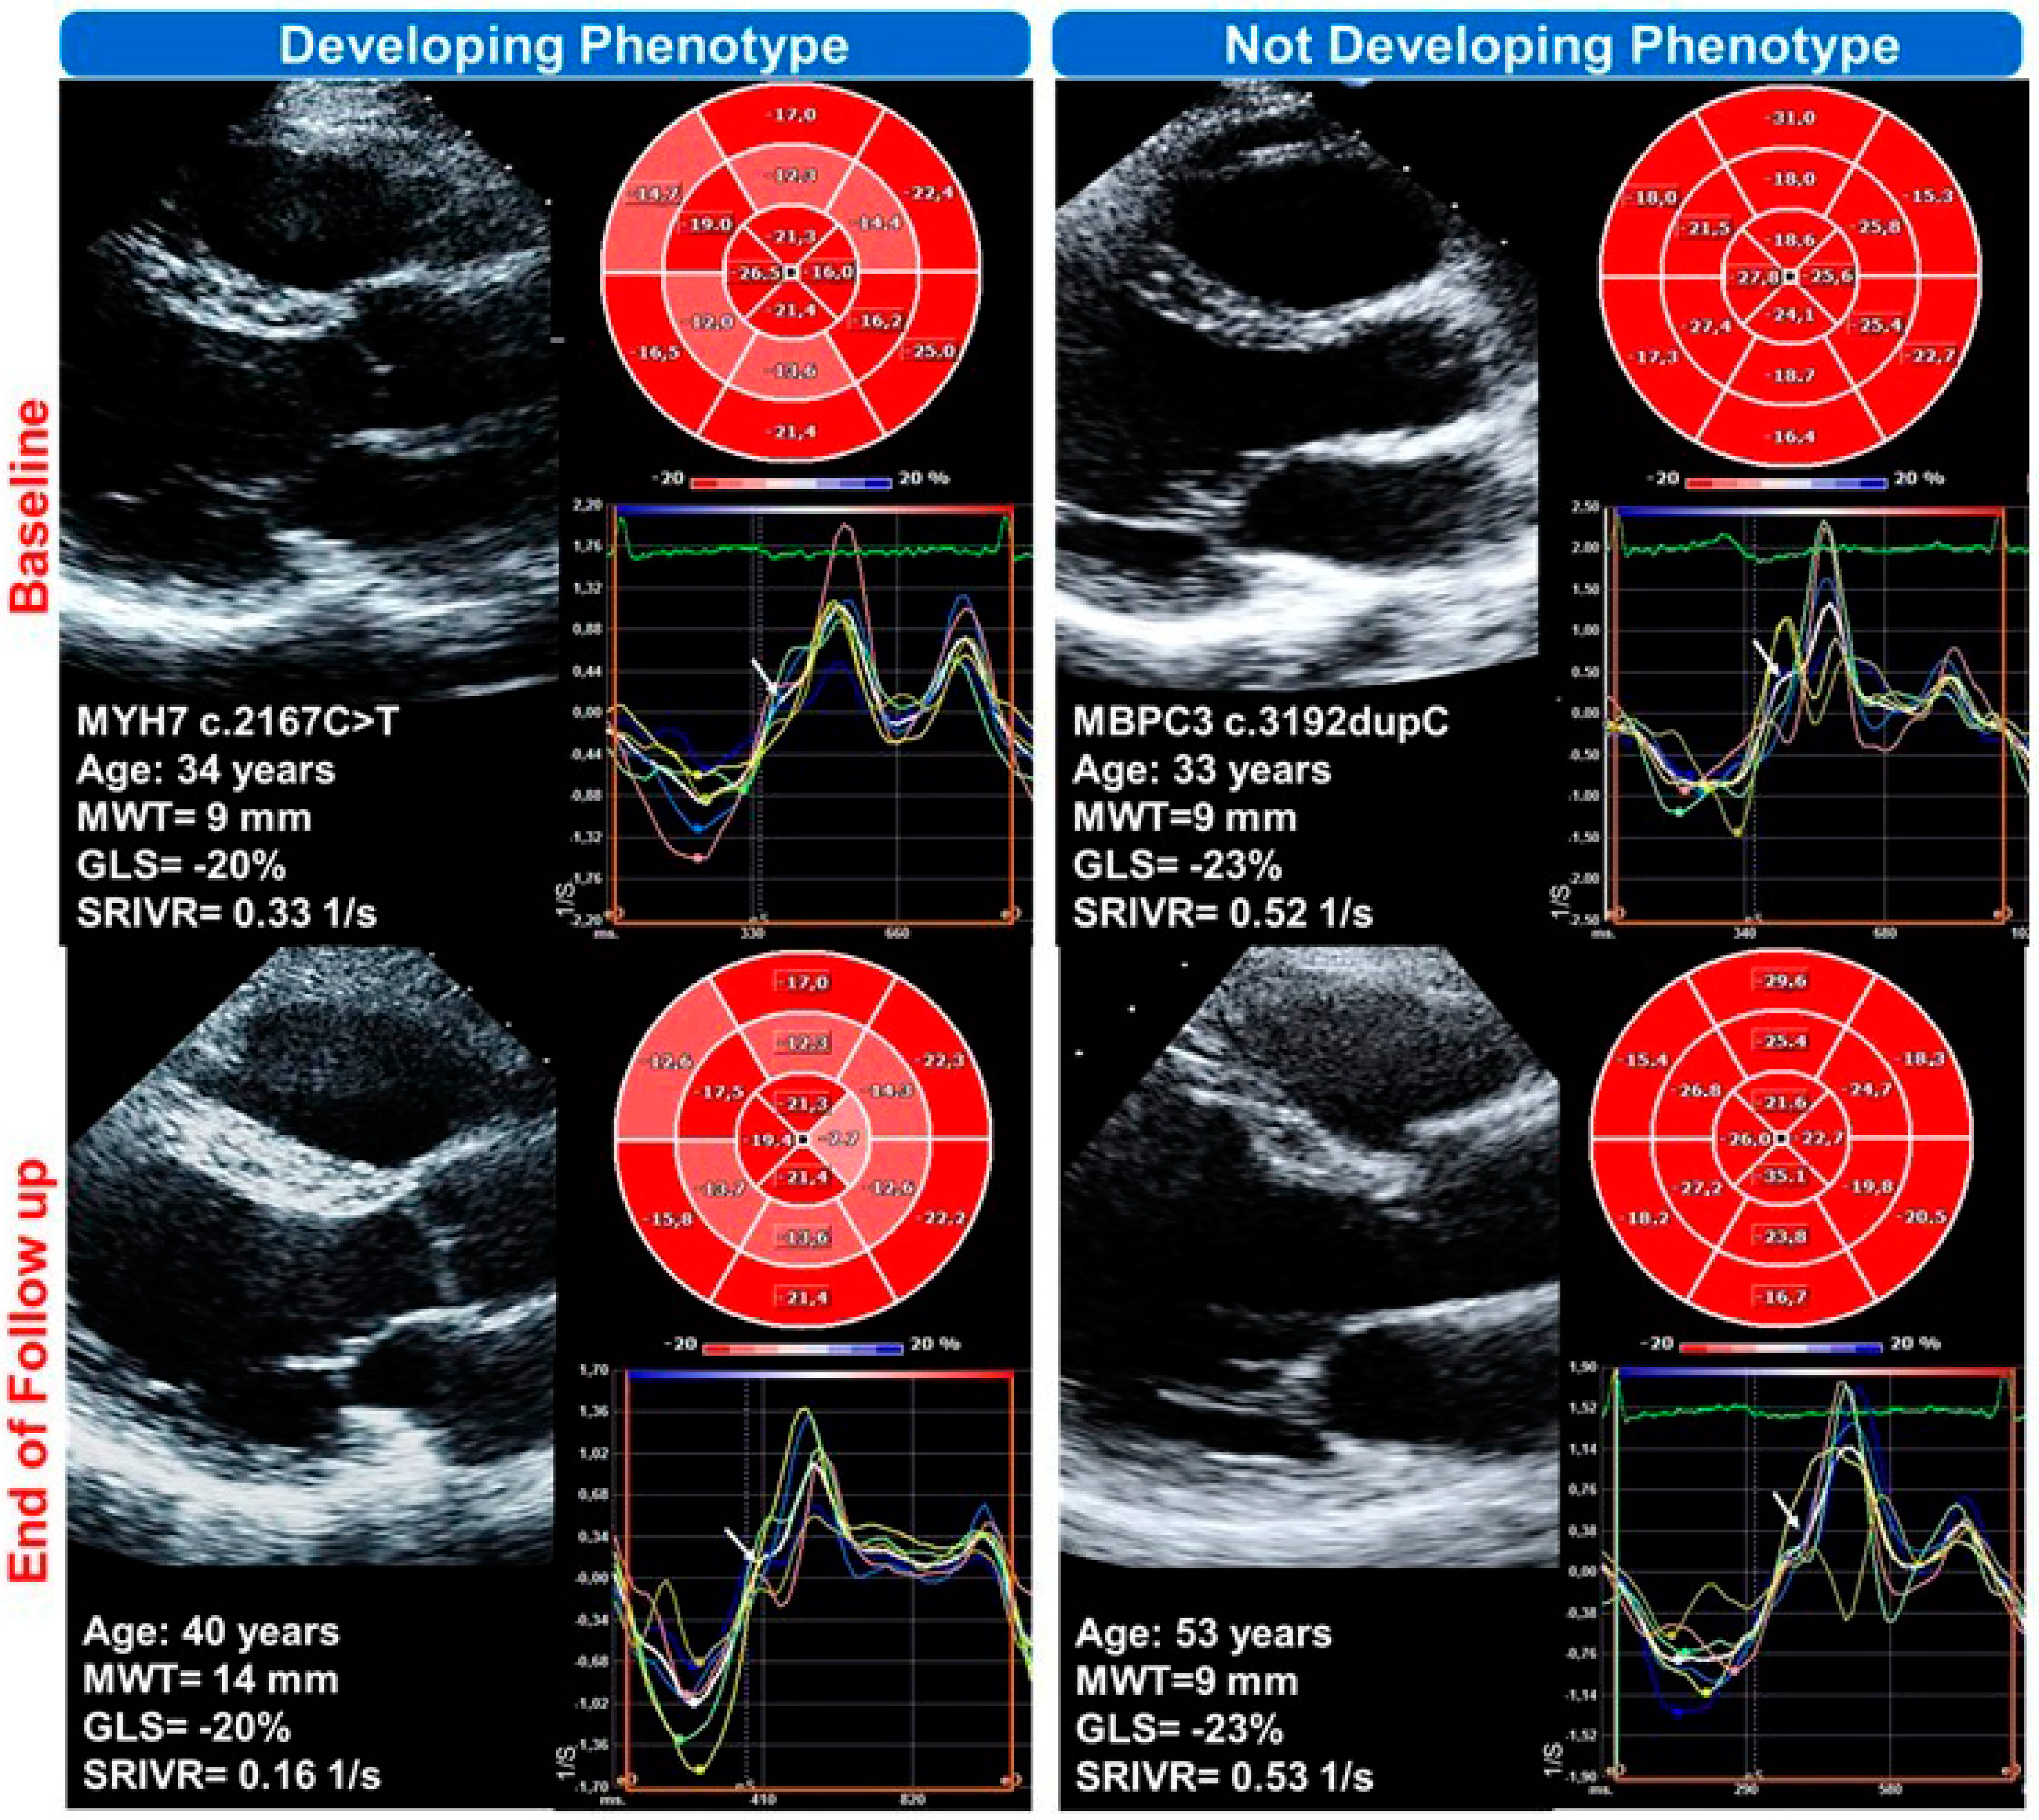

| AB | m | 34 | 1 | Son | MYH7 | c.2167C > T (p.R723C) | 40 | yes |

| VC | f | 33 | 12 | Sister | MYBPC3 | c.3192dupC (p.K1065QfsX12) | 54 | no |